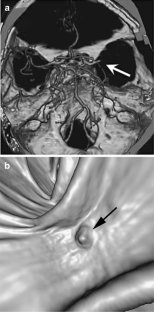

Fig 2.